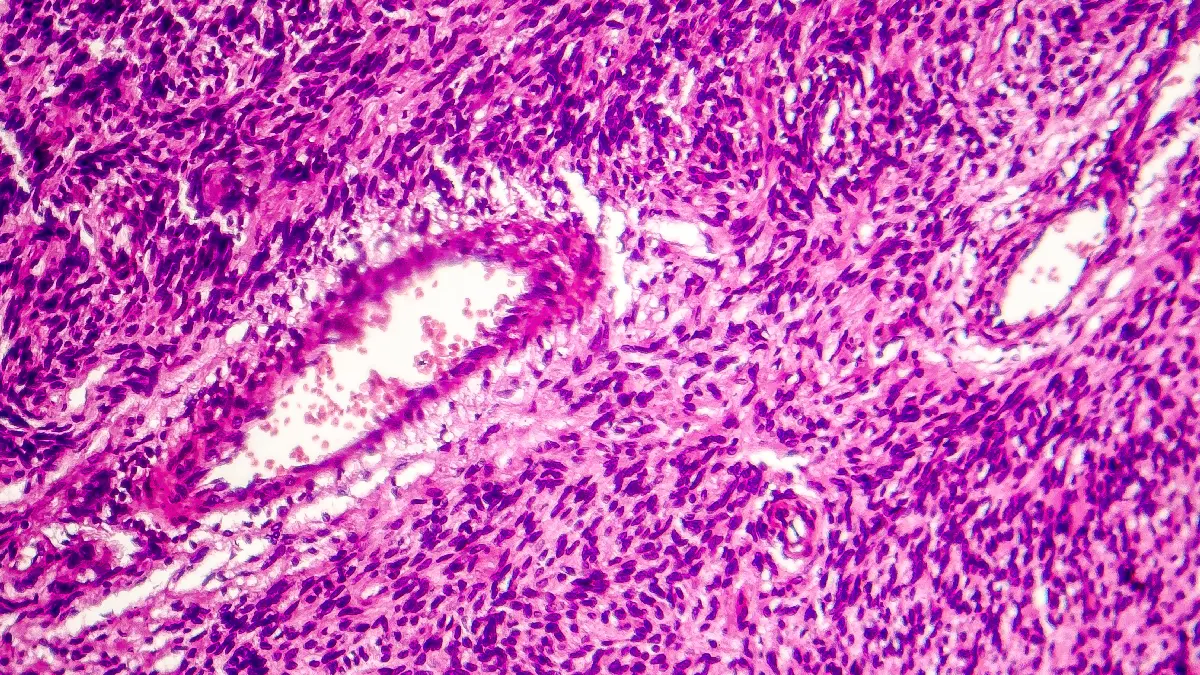

Verbesserte Behandlungsmöglichkeiten bei Weichteiltumoren